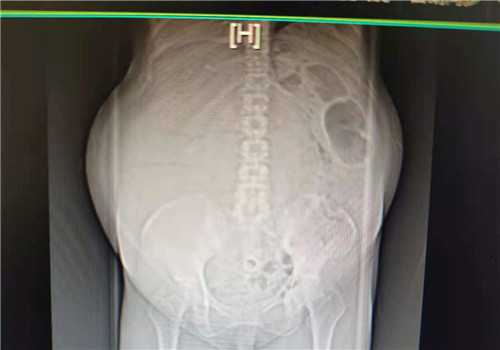

重庆高楼林立,重庆夜景华丽,重庆医护人员温情暖心……重庆给68岁的黑龙江患者张士诚(化名)留下的印象,将可能是终身难忘。本来是想到重...